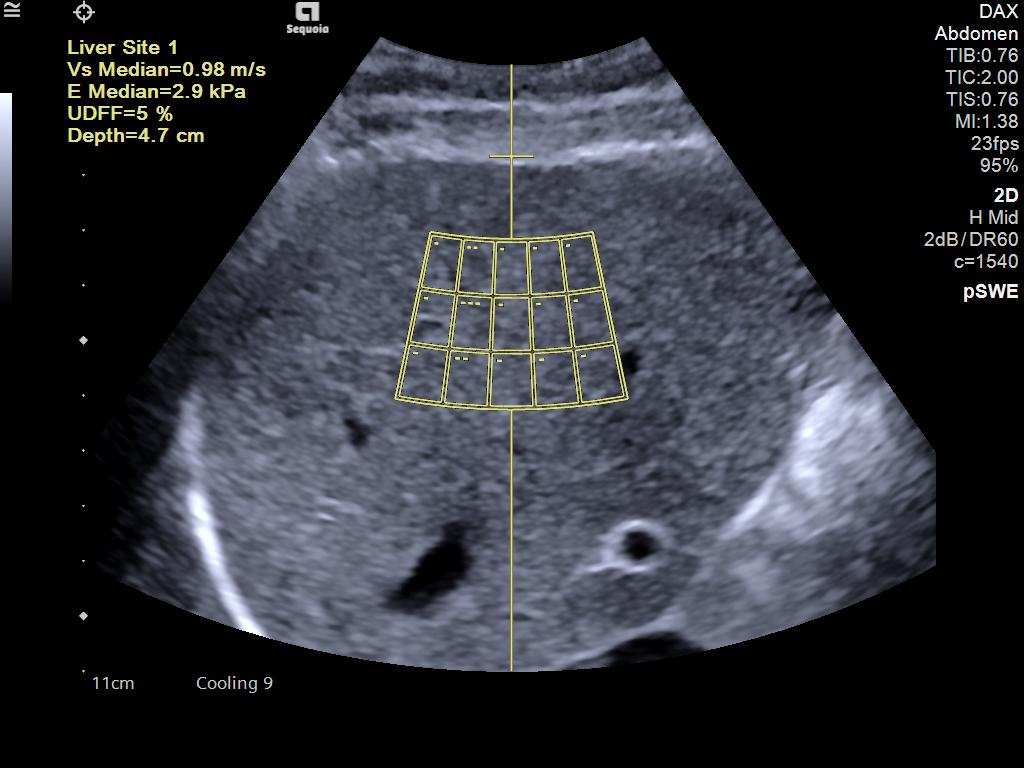

- AI Abdomen automatically recognizes and labels 17 anatomical views and 12 routine measurements.

- Ultrasound Derived Fat Fraction (UDFF) for quantitative ultrasound for liver disease assessment.

- Auto pSWE to reduce liver elastography exam time by up to 75%*.